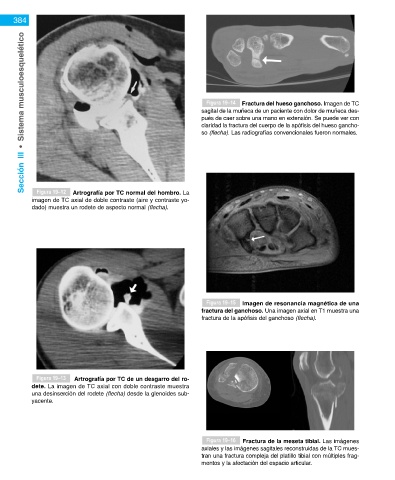

Figura 19–14

Fractura del hueso ganchoso. Imagen de TC

pués de caer sobre una mano en extensión. Se puede ver con

claridad la fractura del cuerpo de la apófisis del hueso gancho-

so (flecha). Las radiografías convencionales fueron normales.

Figura 19–12

Artrografía por TC normal del hombro. La

imagen de TC axial de doble contraste (aire y contraste yo- Figura 19–18 Imagen de resonancia magnética (RM) de

dado) muestra un rodete de aspecto normal (flecha). una miositis osificante. La imagen axial en T2 muestra una

Figura 19–15 Imagen de resonancia magnética de una extensión de las fracturas y para identificar una pato-

fractura del ganchoso. Una imagen axial en T1 muestra una logía intraarticular.

fractura de la apófisis del ganchoso (flecha).

Figura 19–13 Artrografía por TC de un desgarro del ro- TC a través de la masa muestra calcificaciones circunferen-

dete. La imagen de TC axial con doble contraste muestra ciales, periféricas, características de miositis osificante. La

una desinserción del rodete (flecha) desde la glenoides sub- biopsia de una miositis osificante puede parecerse a un diag-

yacente. nóstico de cáncer.

Figura 19–16 Fractura de la meseta tibial. Las imágenes

axiales y las imágenes sagitales reconstruidas de la TC mues-

tran una fractura compleja del platillo tibial con múltiples frag-

mentos y la afectación del espacio articular.